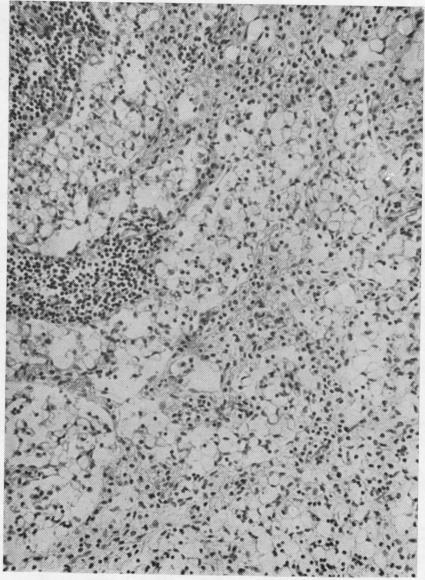

The pathology and chemistry of a case of gargoylism.

J Clin Pathol. 1956 Nov;9(4):305-15. doi: 10.1136/jcp.9.4.305.